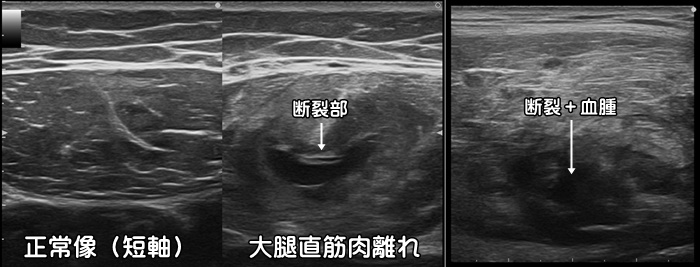

大腿四頭筋の肉離れ

ダッシュ動作や急な方向転換で太ももの前面に痛みを感じた場合、大腿四頭筋と呼ばれる4つの筋肉のうち、大腿直筋と呼ばれる筋肉に肉離れが起こっているかもしれません。エコーでは筋肉の断裂と血腫が確認できます。